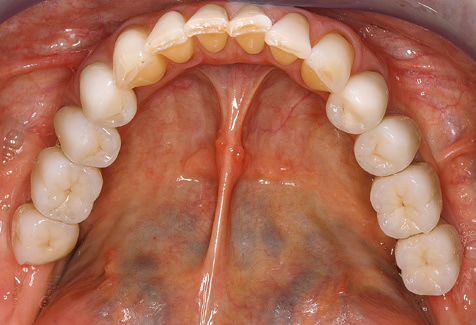

A 52-year-old patient presented in our clinic for the first time in 2004 following tooth loss in the third quadrant, expressing a desire for a new prosthetic restoration. Periodontal and radiological diagnostics revealed the need for extensive periodontological treatment. In addition, teeth 48, 28 and 27 were attributed a very poor prognosis and were subsequently extracted (Fig. 1). Following the successfully completed, systematic periodontological treatment, a fixed dental implant was inserted with the introduction of five implants in tooth regions 35, 36, 37, 46 and 47. Prosthetic treatment of the natural teeth was effected with veneered zirconium dioxide ceramic crowns; the implants were composed of two-piece, individual zirconium dioxide abutments and similarly veneered crowns made of a zirconium dioxide ceramic (Cercon base colored, Dentsply Sirona Lab). Definitive insertion of the prosthetic restoration occurred in 2005.

Due to the presence of periodontal disease, SPT was performed every three months in the first years following the insertion. The patient demonstrated a high degree of motivation and good compliance. The pocket depths recorded annually revealed a stable periodontal situation with a BOP index of below five per cent. On the basis of the stable periodontal situation and good cooperation on the patient’s part, the recall interval was extended to every six months as of the sixth year of the prosthetic function phase. Following the change in the recall interval, the respective annual documentation of the periodontal status continued to reveal a stable periodontal situation with no increase in the pocket depths and a BOP index below five per cent (Fig. 2a and b).

Standardised and regular risk-adapted care in the scope of SPT is the key to treatment success for the clinical long-term success in periodontically compromised patients. This is particularly true for patients fitted with implants following successfully completed periodontal treatment (Fig. 11a and b).